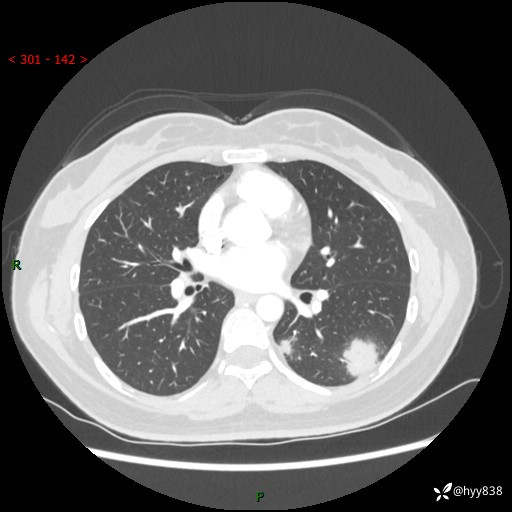

36岁/女,左侧下胸部阵发性疼痛2周,乏力1周。精彩无限,等你来诊---结果公布~

【患者信息】:36岁/女

【主诉】:左侧下胸部阵发性疼痛2周,乏力1周

【现病史及既往史】:患者自诉2周前饮酒后出现左侧下胸部阵发性疼痛,不随呼吸改变,无咳嗽咳痰、头晕头痛、咳血、呼吸困难等不适,于当地第一人民医院查胸部CT提示肺部感染,随后前往我院门诊给予抗感染(左氧氟沙星)治疗1周,自诉胸痛较前好转,感乏力、头晕,偶尔干咳,无咳痰,无发热、畏寒、胸闷、咯血、四肢酸痛、腹泻、腹痛等不适,门诊复查胸部CT提示:左肺下叶感染,病灶较前增加增大,遂以“肺部感染”收入我科。 起病以来,患者精神、饮食、睡眠可,大小便正常,体力体重无明显变化。

【检查】:胸部CT增强(外院平扫)